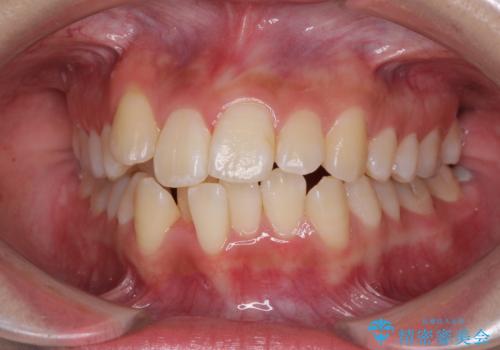

- 八重歯を気にして来院された患者様です。

上下ともに前突感と叢生が認められ、上顎の正中が著しく右側にずれていたため、上下左右第一小臼歯4本を抜歯し、ワイヤー矯正にて治療を行うこととしました。